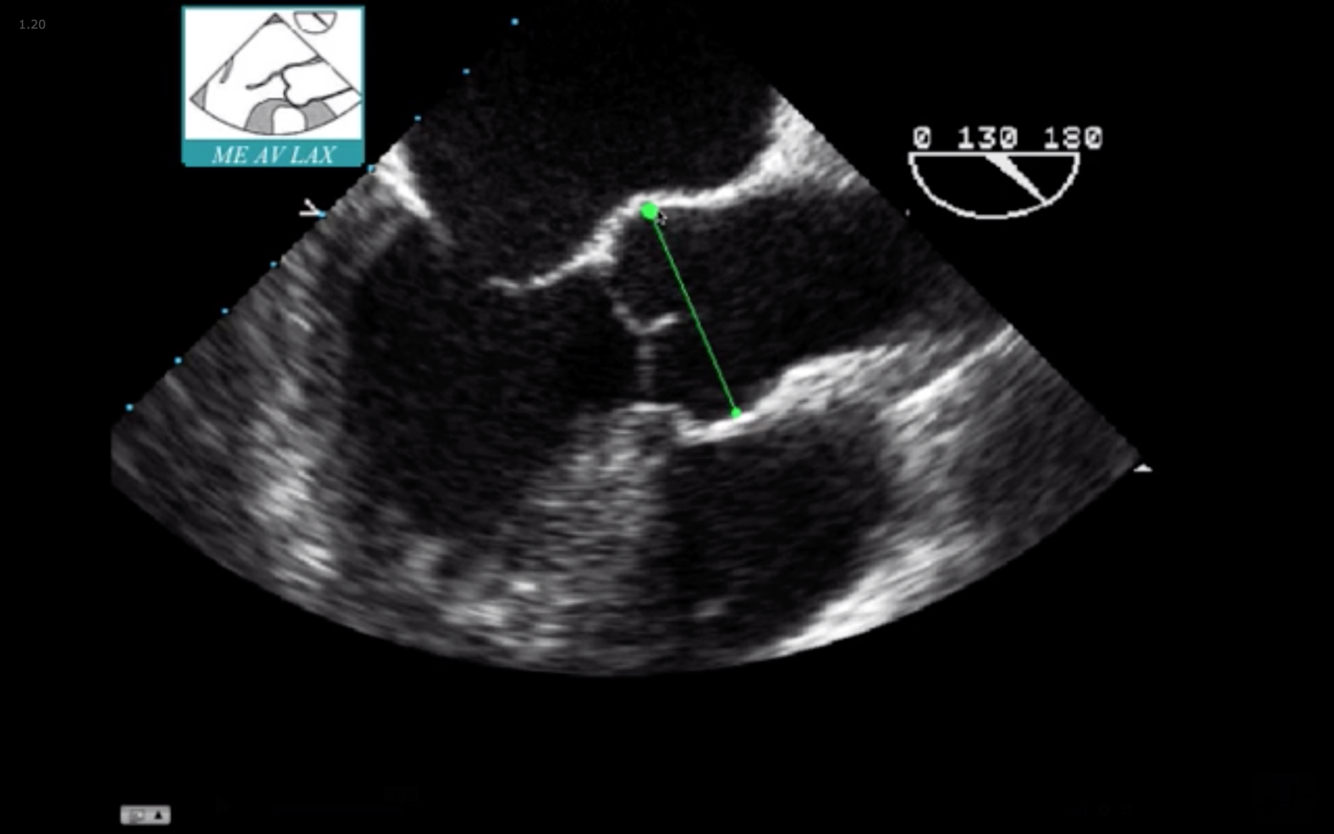

Sinus of Valsalva is in Green

Junction in Teal